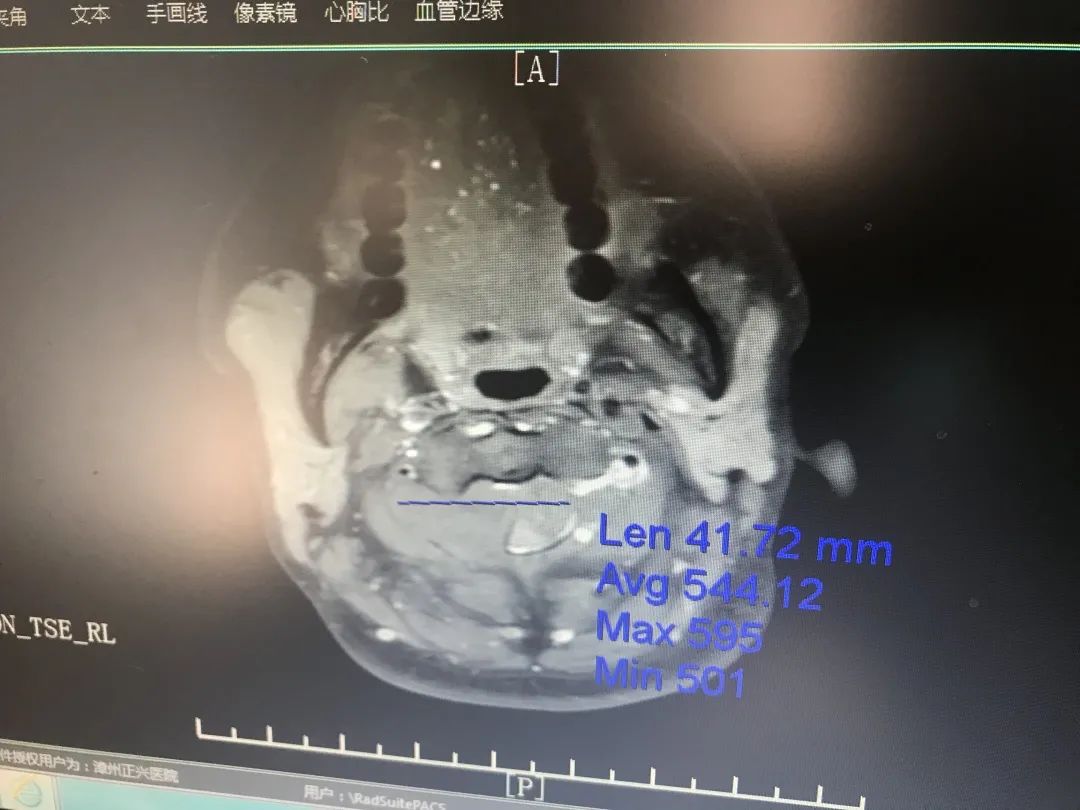

經(jīng)相關(guān)檢查后確診小梅患有“高頸段胸段椎管內(nèi)外多發(fā)性神經(jīng)纖維瘤”。神經(jīng)纖維瘤是指起源于神經(jīng)鞘細(xì)胞的一種良性的周圍神經(jīng)瘤樣增生性病變。神經(jīng)纖維瘤雖為一種常見的良性腫瘤,但由于其病程發(fā)展及治療上的特殊性,如瘤體可發(fā)展巨大,造成組織器官形態(tài)改變及功能障礙,并可惡變,瘤體血供豐富,完整切除困難,術(shù)后易復(fù)發(fā)等,使其成為臨床上難治的疾病。

△術(shù)前磁共振影像